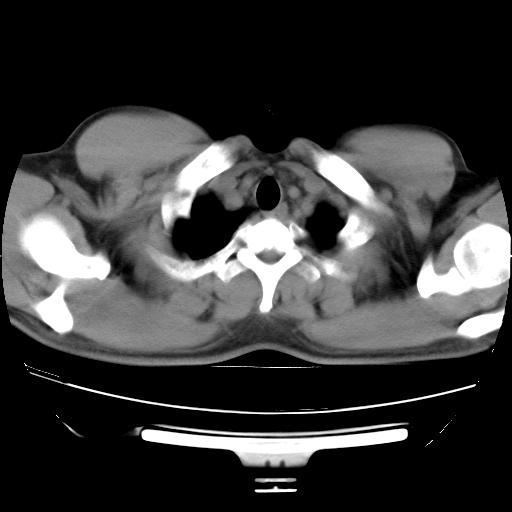

男,38岁,于2009年8月9日晚突发左侧胸痛,今x线提示左下肺阴影,为了明显确诊断,行ct检查,

血常规:嗜酸性细胞增高,单核细胞增高。

纵膈窗

病灶发生在下叶,密度均匀,边缘模糊、毛糙,周围血管纹理增强扭曲改变,靠近胸膜处病灶胸膜反应明显。

支持考虑---球形肺炎。

左肺舌叶病变。主体病灶呈类圆形中心密度低,成液化趋势周边班片影分布

考虑肺脓肿

虽然实验室检查支持炎性病变,且病变内有坏死改变(中央呈大片状低密度影),但仍不能掉以轻心,鳞癌也可以有这种影像改变。